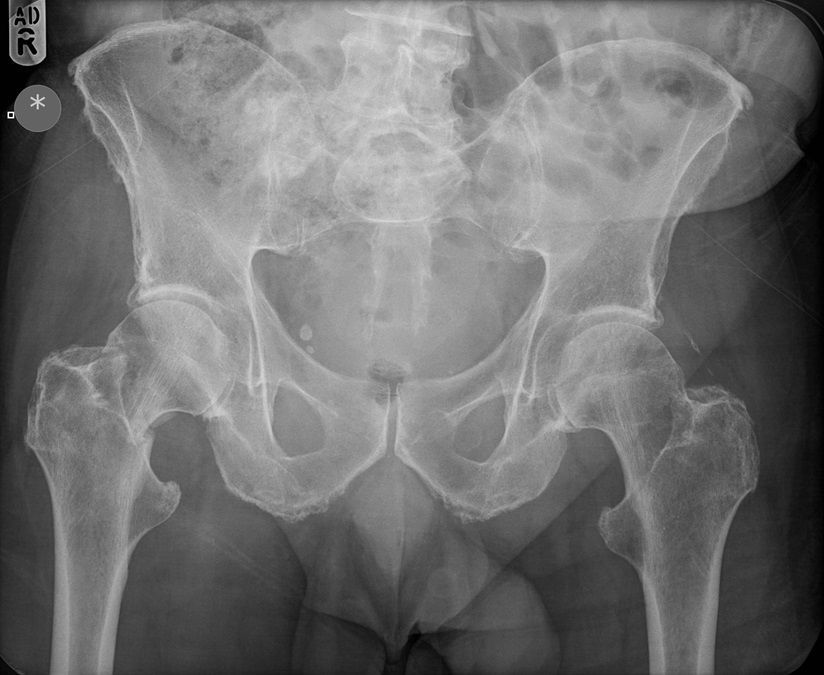

Question 3

Question

Which operation would you perform?

Answer

• THR

• Hemiarthroplasty